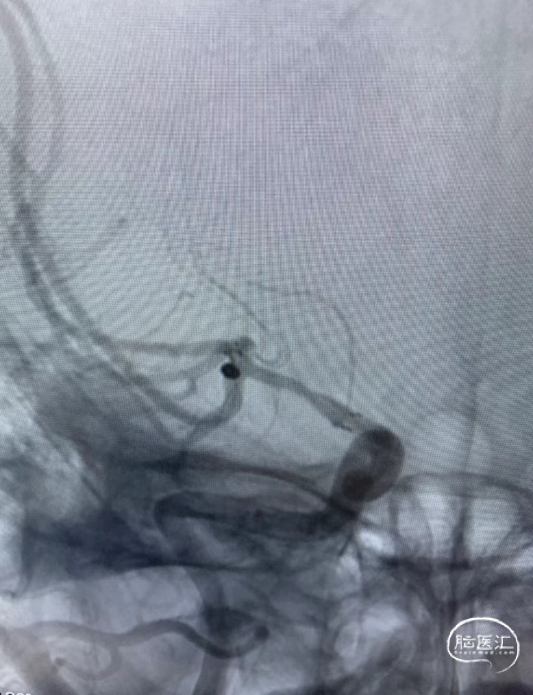

患者一期治疗使用Neuroform EZ支架重塑右侧大脑中M1狭窄段,但支架远端定位落于中干,紧邻动脉瘤开口处,故封堵动脉瘤瘤颈的支架只能穿过第一枚支架的网孔释放于下干支。

为充分保护分支血管使手术顺利进行,拟释放一枚LEO+Baby支架于下干支,与Neuroform EZ支架形成“T型”,既能很好地保护瘤颈,也能避免做“Y型”时支架交叉及重叠区域打开不良。

支架微导管到位后,释放支架。

支架释放后,送入首枚2*4的弹簧圈栓塞动脉瘤。

送入第二枚1.5*2的弹簧圈致密栓塞动脉瘤。

术后造影显示动脉瘤致密栓塞,不再显影;其它各分支血管通畅。

术后造影模拟血管重建显示支架头端完全覆盖动脉瘤瘤颈,并且与一期释放的支架远端形成“Kissing”。